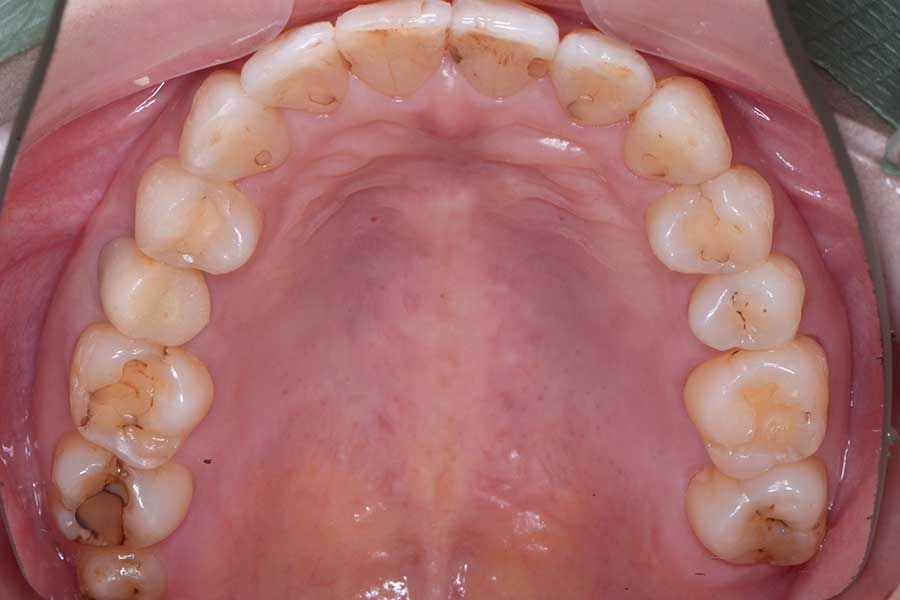

治療後

主訴 前歯の虫歯治療の前に飛び出た前歯を引っ込めたい

期間 7か月

治療内容 上顎ラビアル矯正(表側矯正)